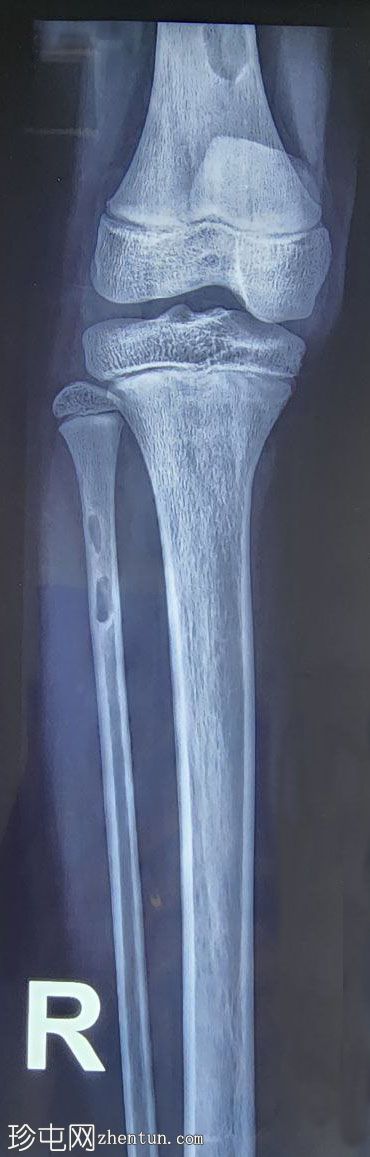

X光片

正面

右股骨远端干骨干和腓骨近端可见边界清晰的偏心溶骨性病变,可见狭窄的过渡区和较薄的硬化边缘。无明显骨折。这些影像学表现可能提示多发性局灶性皮质缺损或非骨化性纤维瘤。